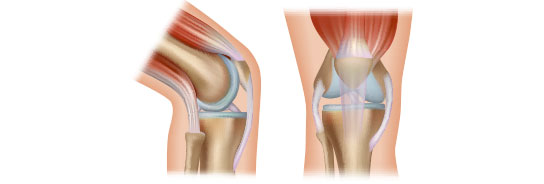

인대 재건술은 관절의 인대가 손상되었거나 파열되었을 경우 시행하는 수술법입니다. 전방/후방십자인대, 내/외측 측부인대 등 무릎 관절이 외부 충격이나 손상으로 제 기능을 상실한 경우 새로운 인대를 이식하여 원래의 기능을 되찾아주는 방법입니다. 인대 파열 시 발생하는 인대 강도의 약화, 길이 변화에 대해 가장 확실하게 본래의 기능을 회복시켜주는 수술입니다.

1. 관절경을 이용하여 인대의 위치와 손상 정도를 확인하고, 파열된 인대를 정리합니다.

2. 인대가 삽입될 터널 만들기 - 대퇴골과 경골에 이식건을 삽입할 구멍을 만듭니다.

3. 인대삽입 - 터널 구멍에 이식건을 통과시켜 연결 후 양쪽 뼈에 이식건을 고정하여 재건합니다. 타가건을 이용할 경우 잔존 인대조직을 덧대어 이식함으로써 회복을 앞당기고, 더욱 튼튼하게 재건되도록 돕습니다.